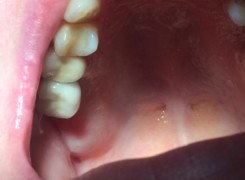

Pan Ryszard trafił do Naszego Gabinetu z jasno sprecyzowanym oczekiwaniem. Miał 84 lata i chciał odzyskać możliwość swobodnego spożywania posiłków oraz poprawienia sobie komfortu życia a także prosił aby przywrócić mu piękny uśmiech jakim cieszył się przed laty. Już na początku pierwszej rozmowy zastrzegł, że interesuje go wyłączenie rozwiązanie uzupełnieniem protetycznym stałym. Nie miał zamiaru użytkować żadnych protez ruchomych. Mając na uwadze powyższe wykonaliśmy Panu Ryszardowi zdjęcie pantomograficzne oraz badanie tomograficzne szczęki i żuchwy na postawie których zapanowywaliśmy Pacjentowi optymalne rozwiązanie – stałe uzupełnienie protetyczne w postaci 28 koron cyrkonowych zamontowanych do dwóch belek cyrkonowych które będą przymocowane do 16 implantów w konfiguracji 8 wszczepów w szczęcie 8 w żuchwie. Po omówieniu powyższego planu przystąpiliśmy do Wspólnej pracy której efekty w poszczególnych etapach prezentujemy poniżej.